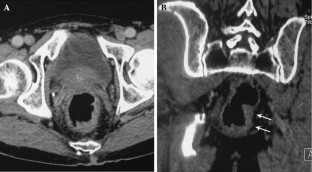

Fig. 1

Fig. 2

Fig. 3

Fig. 4